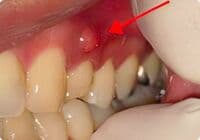

フィステルの画像

フィステル

根尖周囲組織に炎症が波及すると、フィステルといわれる排膿路(歯ぐきにポツリとできたおできの様なふくらみ)が形成されることがあります。